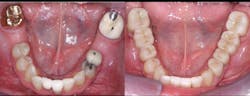

A: Full-zirconia restorations have been available for the past years or so. They have evolved from relatively unesthetic, opaque crowns and bridges to significantly improved restorations with acceptable esthetics (figures 1 and 2). Most dentists have noted that the majority of zirconia restorations are lighter in color than they requested on their lab order. The intense opacity of this material makes the restorations appear light in color. As the new generation of "esthetic zirconia" restorations continues to improve, this color problem will probably be overcome.

Figure 2: Full-zirconia restorations on the first and second molars show the significant improvement in color now available with full-zirconia restorations.